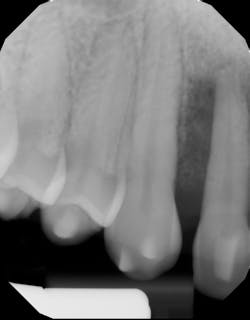

Another scenario that took place in a private practice with actual dollar amounts can be seen in treatment plan C. This patient had already paid for treatment plan B in the $5,000–$7,000 range and subsequently presented to the practice with moderate peri-implantitis. In addition to the money the patient had already invested, she would now be responsible for the financial costs of treatment plan C.

After reviewing the additional costs and lengthy healing time involved with surgery to correct the ailing implant, the overall costs associated with treatment were in the $8,000–$10,000 range, with more than three years of treatment time invested. Of important note is that most insurance companies limit the amount of reimbursement for implant-related services. When dealing with insurance companies, accurate ADA coding and claims submission are critical to facilitate services and expedite reimbursement.